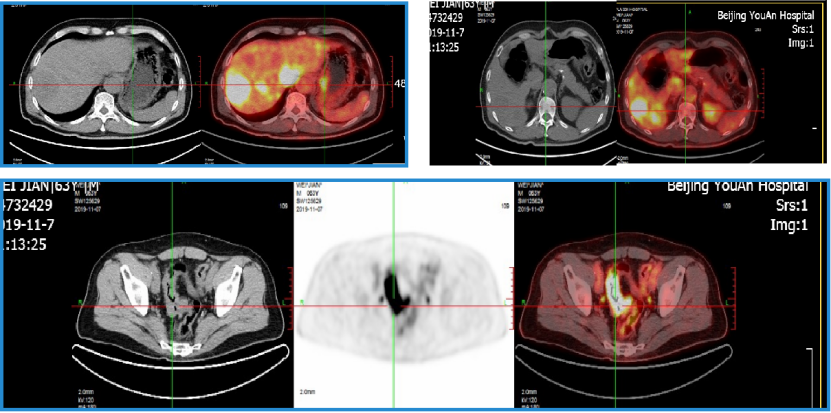

2019年11月7日 行PET-CT:

1. 乙状结肠部位高代谢病变,肝内多发高代谢灶,左肺上叶尖后段高代谢结节,以上均考虑恶性,乙状结肠癌伴左肺及肝脏转移可能性大。

右肺上叶局限性肺气肿改变;右肺门稍高代谢淋巴结,多考虑炎性反应淋巴结。

PET-CT影像